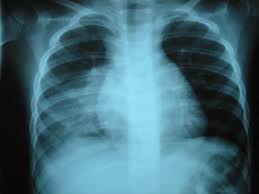

Alteracion en Rx torax.

Enfermedades Pulmonares Obstructivas Cronicas

Trastorno pulmonar, que se caracteriza por la existencia de un obstrucción de las vías aéreas generalmente progresiva y en general no reversible. Generalmente, esta causada por el Humo Del Cigarrillo y produce como síntoma principal una Disminución de la capacidad respiratoria, que avanza lentamente con el paso de los años y ocasiona un deterioro considerable en la calidad de vida de las personas afectadas, seguido de una muerte prematura.

Comparativa entre Pulmones Sanos y Pulmones con EPOC